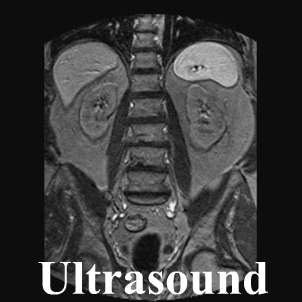

Medical imaging

Medical imaging includes ultrasounds, computed tomography or magnetic resonance imaging.

X-ray exams of the adrenal and pituitary glands may also be useful to help understand the underlying cause to Addison's disease. However these x-rays or ultrasonic scan of the adrenals is most likely to only show calcification, and is therefore probably not useful unless there is a strong suspicion of TB. Adrenal antibodies are likely to be positively associated with Addison’s disease but this cannot always be seen.

Ultrasound image of the adrenal glands modified image courtesy of Flickr under the creative commons license.